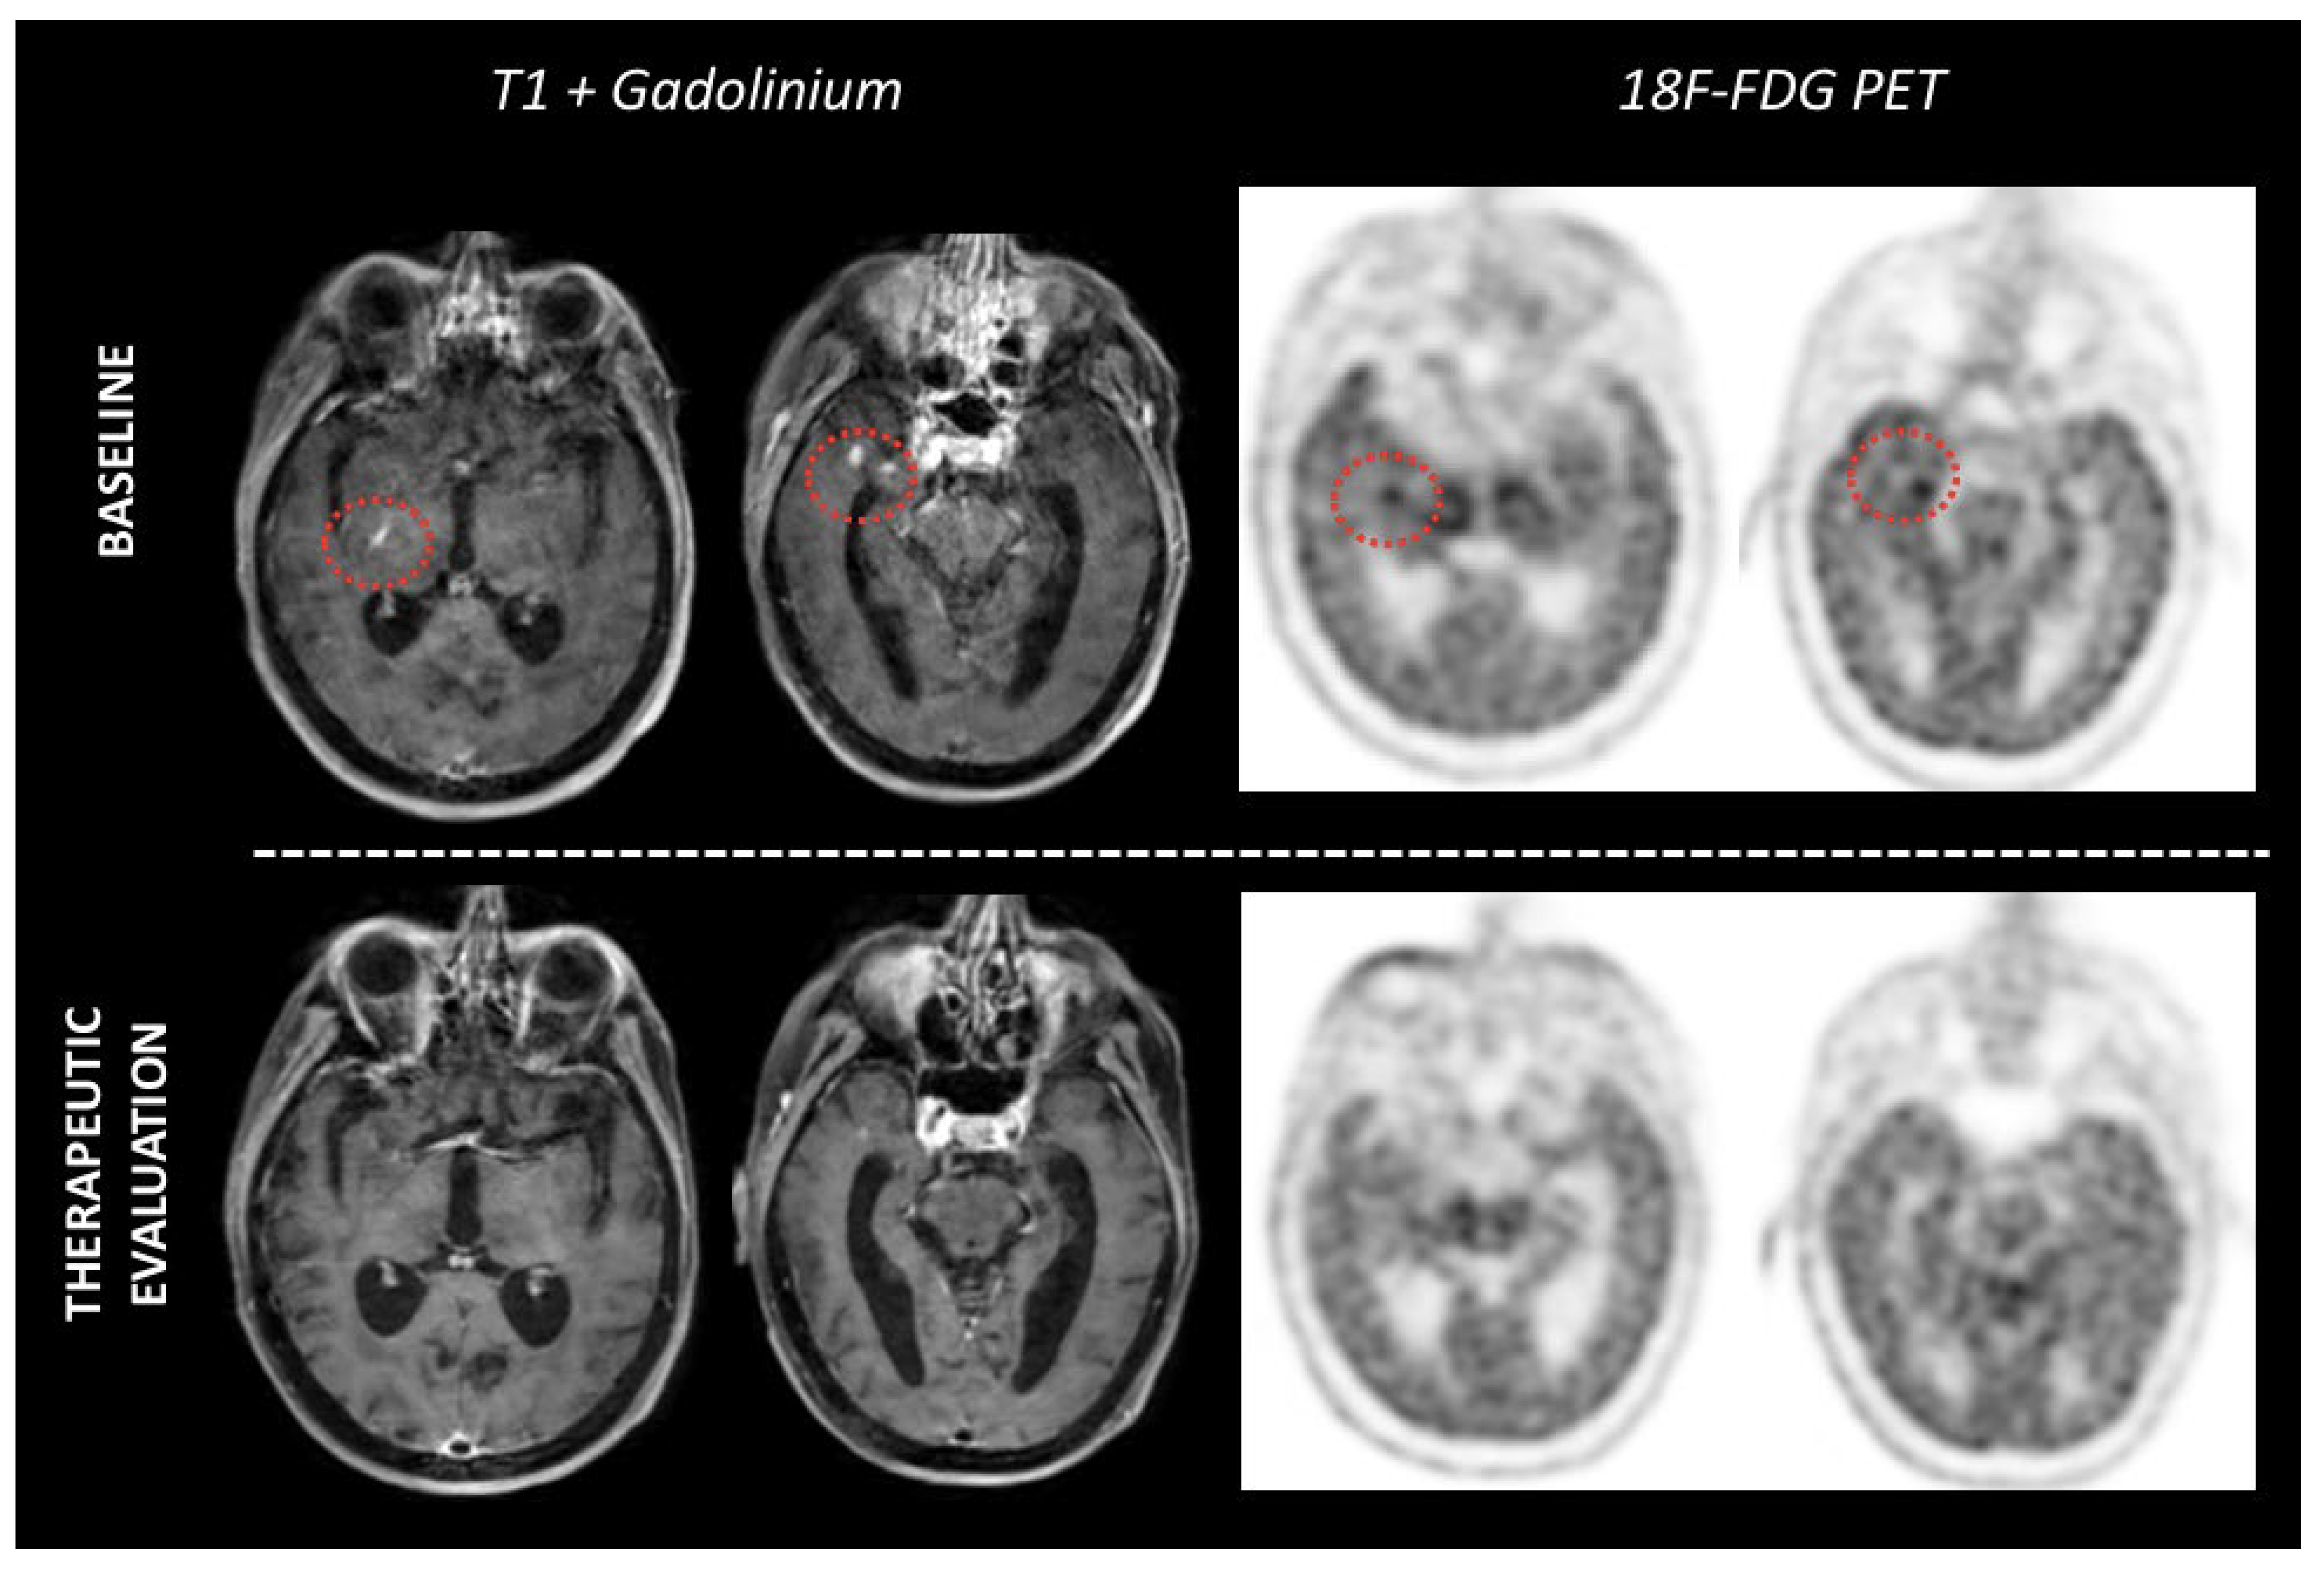

3.2. Therapeutic Evaluation

4. Others PET Tracers in PCNSL